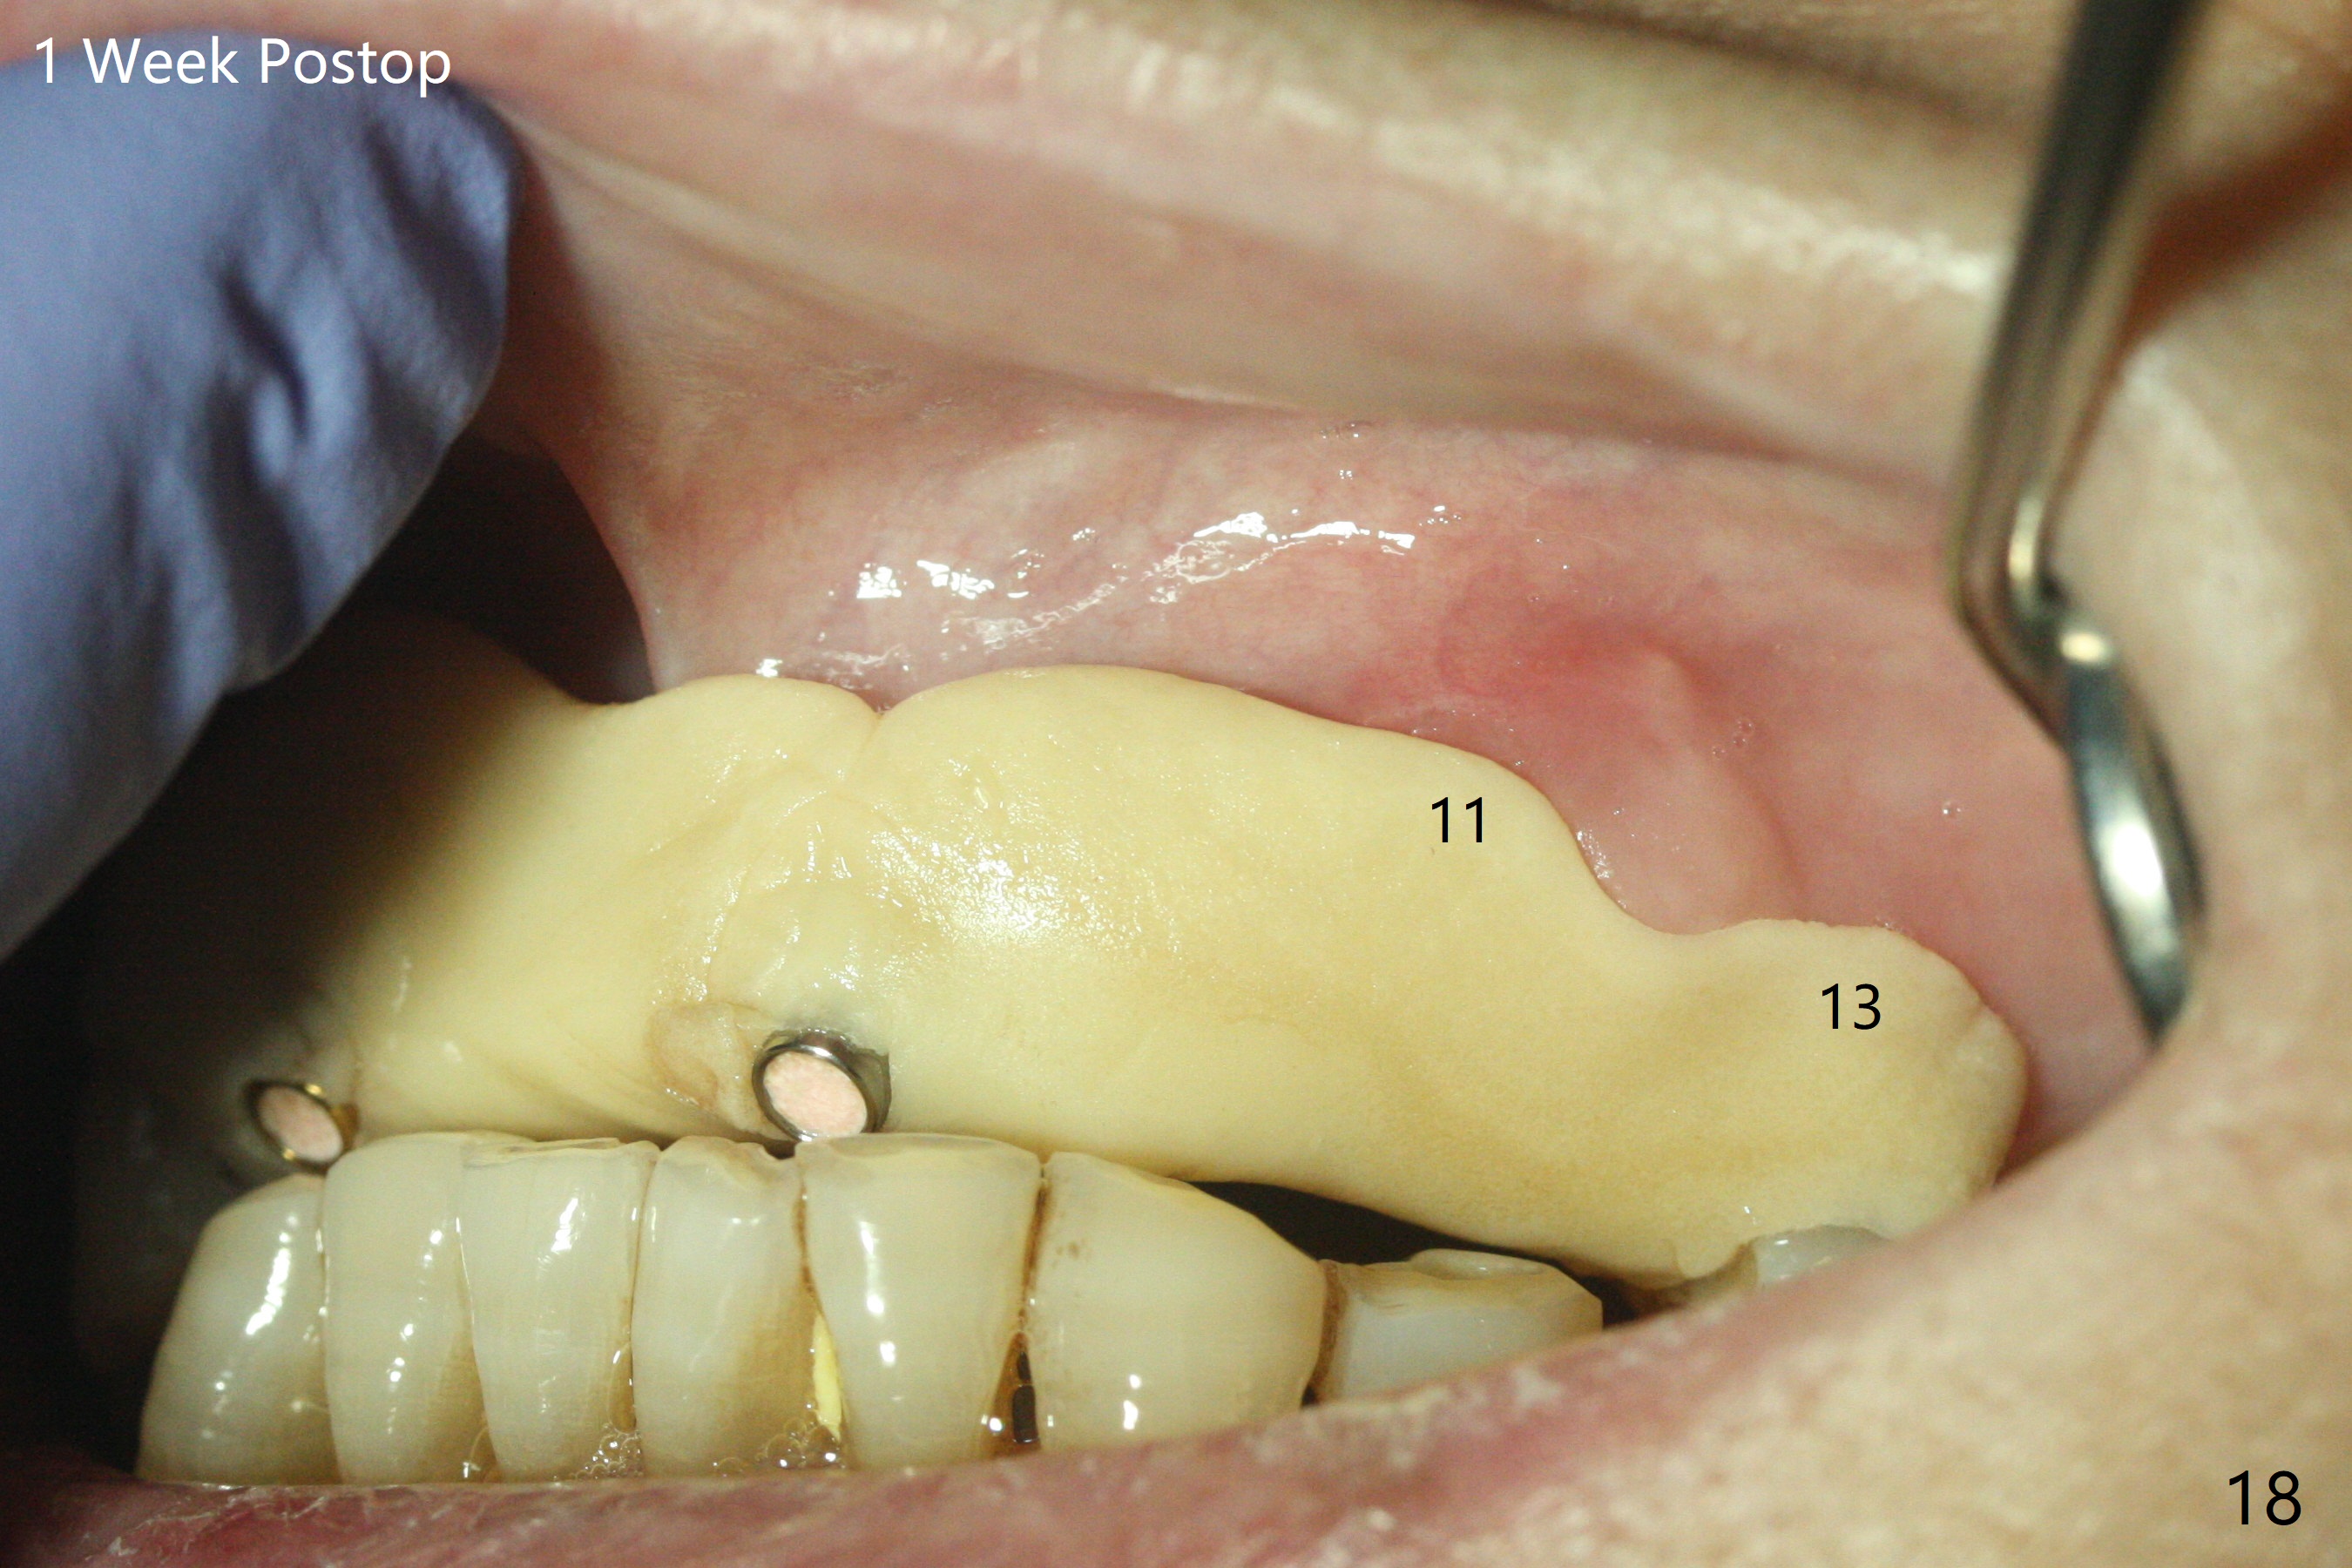

今天下午进入治疗室,粘性骨粉已制备:上清液来自红管(含促凝剂),离心3分钟(图一);再离心10分钟上清液就转变PRF,压制后,使用前剪成三块(图二:黑线),其中两块punch一个洞(图二:圆圈),插入7,9号牙基台固定;大块覆盖11/12号牙牙槽窝(图十四)。7,9,11,12号牙必须拔除(图三),然后在7,9,12种植。由于缺失左下磨牙,前牙垂直距离减少(图四)。完成9号牙位钻洞后,利用fixture mount(图五:M)植入植体,并留在原位固定导板(图六),然后7号牙种植,也留下fixture mount(图六:7,9),最后完成12号牙植入,但是后者扭力低,放置愈合螺帽(图九),而7,9号牙位放置修复基台(图七,八(使用5.5毫米profile drill后),好像基台没有完全就位。7号牙位更换基台似乎没帮助(图十),9号牙位再次放置同一个基台临床上仿佛有改变(比较图八与十二)。放置粘性骨粉后(图十一至十三),牙槽窝口覆盖PRF膜(图十四:P(A:基台)),最后使用树脂敷料固定骨粉和膜(图十五,六),基台帮助敷料固位,没有咬合干扰(图十七:*)。树脂敷料部分解决美观问题,一个月后撤除,如果植体仍有稳定性,可能制作7-10临时牙桥,可能部分维持或者恢复牙龈外形。术后一周病人主诉后面植牙和鼻底疼痛,11号牙根尖牙龈充血(图十八),轻度触痛,可能与术中尚未完全清创有关(图十九(术前CT 3D图像))。再服用Amoxicillin一周,症状好转,鼻底轻度触痛(图二十)。术后1.5月没有任何不适,撤除树脂敷料,7号牙基台(袖)显得太长,换一个短的(4.5x4(5)(图十,十一)->4x4(3)毫米)毫米),植骨好像愈合正常(图二十一:*)。7号牙换了短的基台,9号牙基台高度调整后,与对合牙有足够空间做临时牙桥,最好8,10号牙位牙龈应该凹陷(图二十二:*),有pontic外形。另外9号牙基台颊侧牙龈边缘有所修整,临时牙桥准备。先做7-10临时牙桥,理想临时牙桥pontic处树脂应该多些(图二十三:白线)压迫牙龈形成凹陷。11,12号牙牙槽窝在树脂(Bosworth)敷料下也正常愈合(图二十四)。